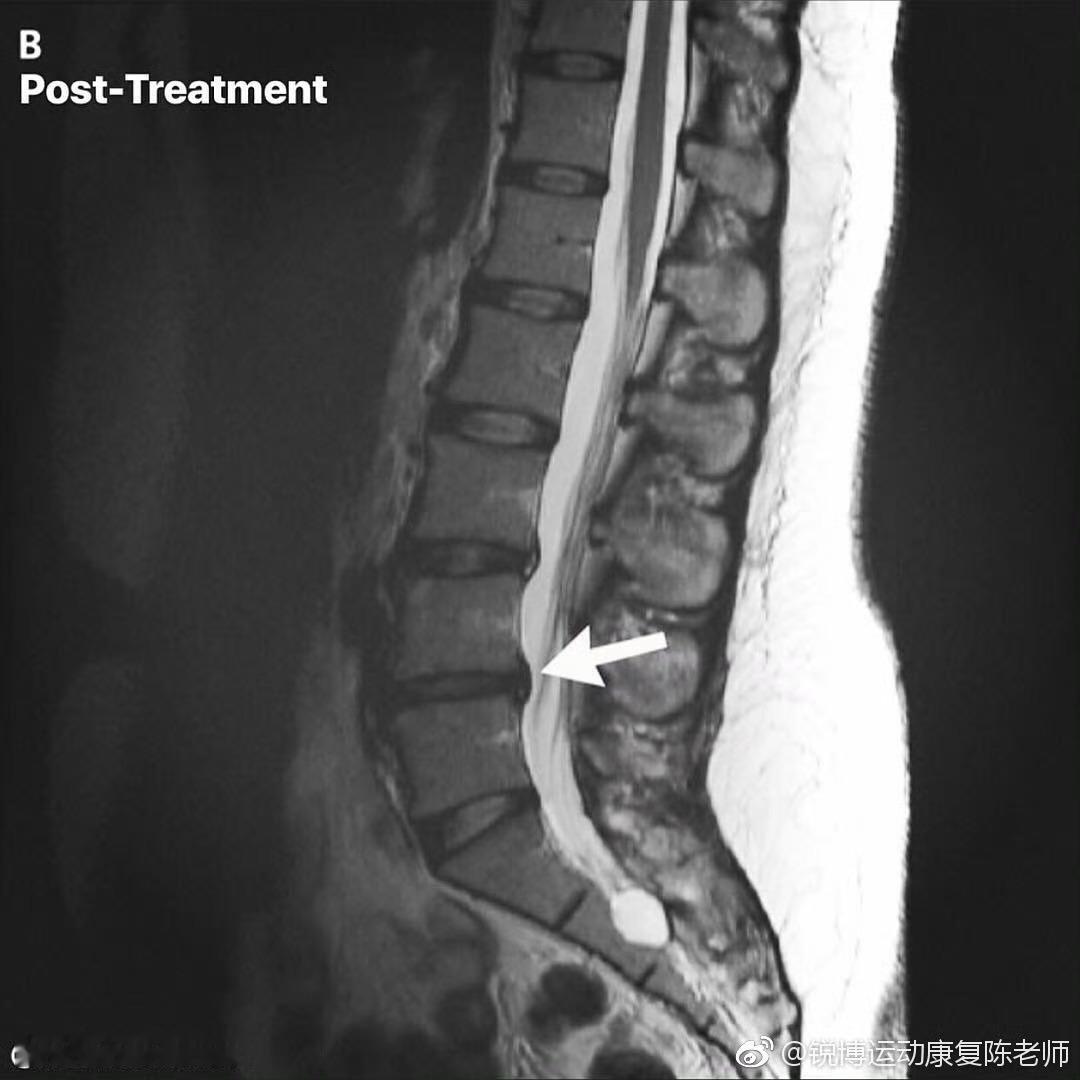

腰突到底是不是病?💡很多人CT查出椎间盘突出就惊慌失措,贴膏药、扎针折腾半天,其实单纯突出不是病!25岁后椎间盘自然蜕变,就像人会衰老,多少有点膨出突出很正常。 只要没明显不适,根本不用过度治疗。真正要做的是养护:少低头弯腰,多练腰背部肌肉,让肌肉给脊柱搭支架。 等到出现脖子疼、腰疼、胳膊麻、腿酸困,说明突出压迫神经变成腰椎间盘突出症,这时候再找医生正规治疗就对了。